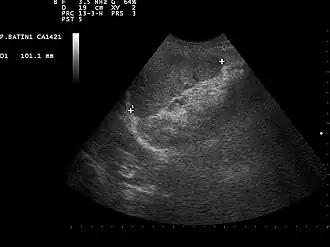

![]() Ultrasound image of a normal spleen that may be seen in part of the eFAST | |

- Left upper quadrant of the abdomen (perisplenic view). Left upper quadrant is examined by working your probe down the midaxillary line starting at the left 8th rib to the 11th rib. This examines for free fluid around the kidney and spleen.